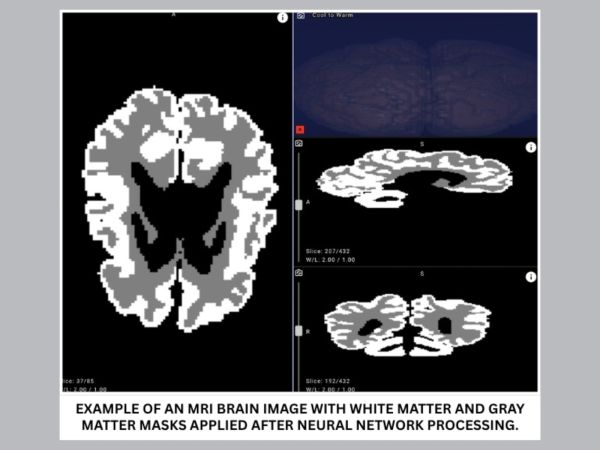

The proposed solution analyzes MRI scans and can distinguish between gray and white brain matter with over 90% accuracy. Cutting evaluation time from days to minutes, it enables earlier detection and more effective rehabilitation planning for infants with cerebral palsy and other central nervous system disorders.

To bridge this gap, Yandex researchers collaborated with medical experts to create new annotations, design a dedicated neural network architecture, and run a series of machine learning experiments. The resulting model achieved over 90% accuracy in distinguishing gray and white matter in infant brains on internal evaluation data, demonstrating its potential for clinical use.

- Improve accuracy and objectivity. With over 90% accuracy, the model highlights outlines and quantifies the ratio of gray to white matter in an infant's brain.